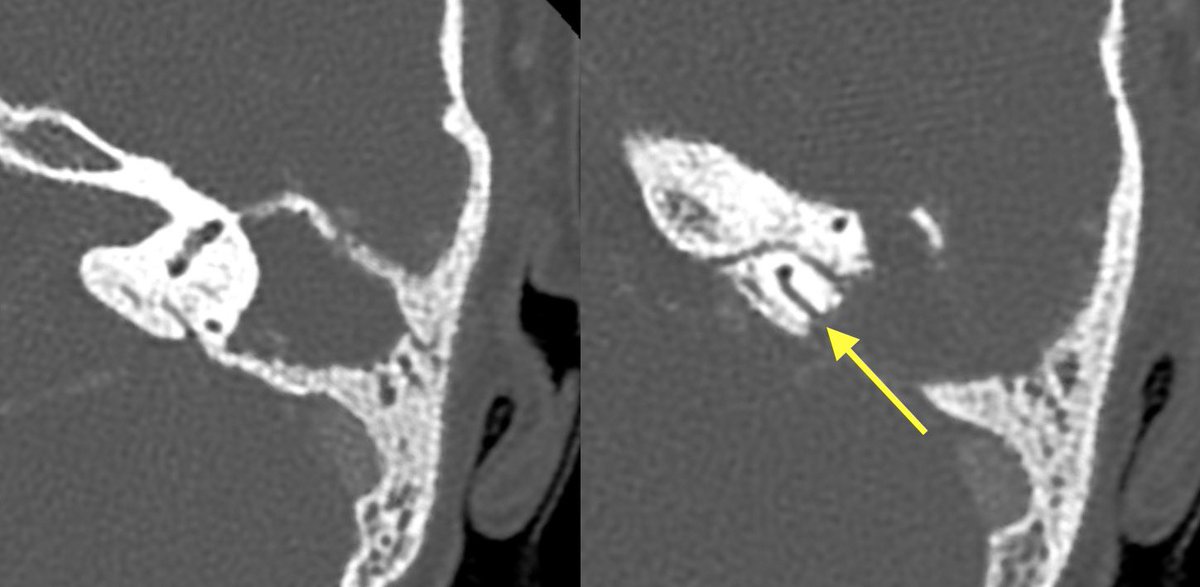

Initial T bone CT:

▶️Coalescence of mastoid air cells

▶️diffuse dehiscence of Tegmen tympani

▶️Middle ear ossicle erosions

▶️dehiscence of the roof of the EAC

▶️dehiscence of semicircular canals and tympanic segment of facial nerve

With findings this extensive it can be difficult to differentiate cholesteatoma from coalescent otomastoiditis

Helpful clues in cholesteatoma

💡 MORE MASS EFFECT (expansion of aditus ad antrum, displacement of middle ear ossicles with enlarged middle ear cavity)

💡 MORE EROSIONS (middle ear ossicles, facial nerve canal, semicircular canals)

💡 More likely to have retracted or ruptured TM

Cholesteatoma was favored in this case given the extent of erosions and lack of significant surrounding inflammatory change. However, symptoms were concerning for superimposed infection and meningitis